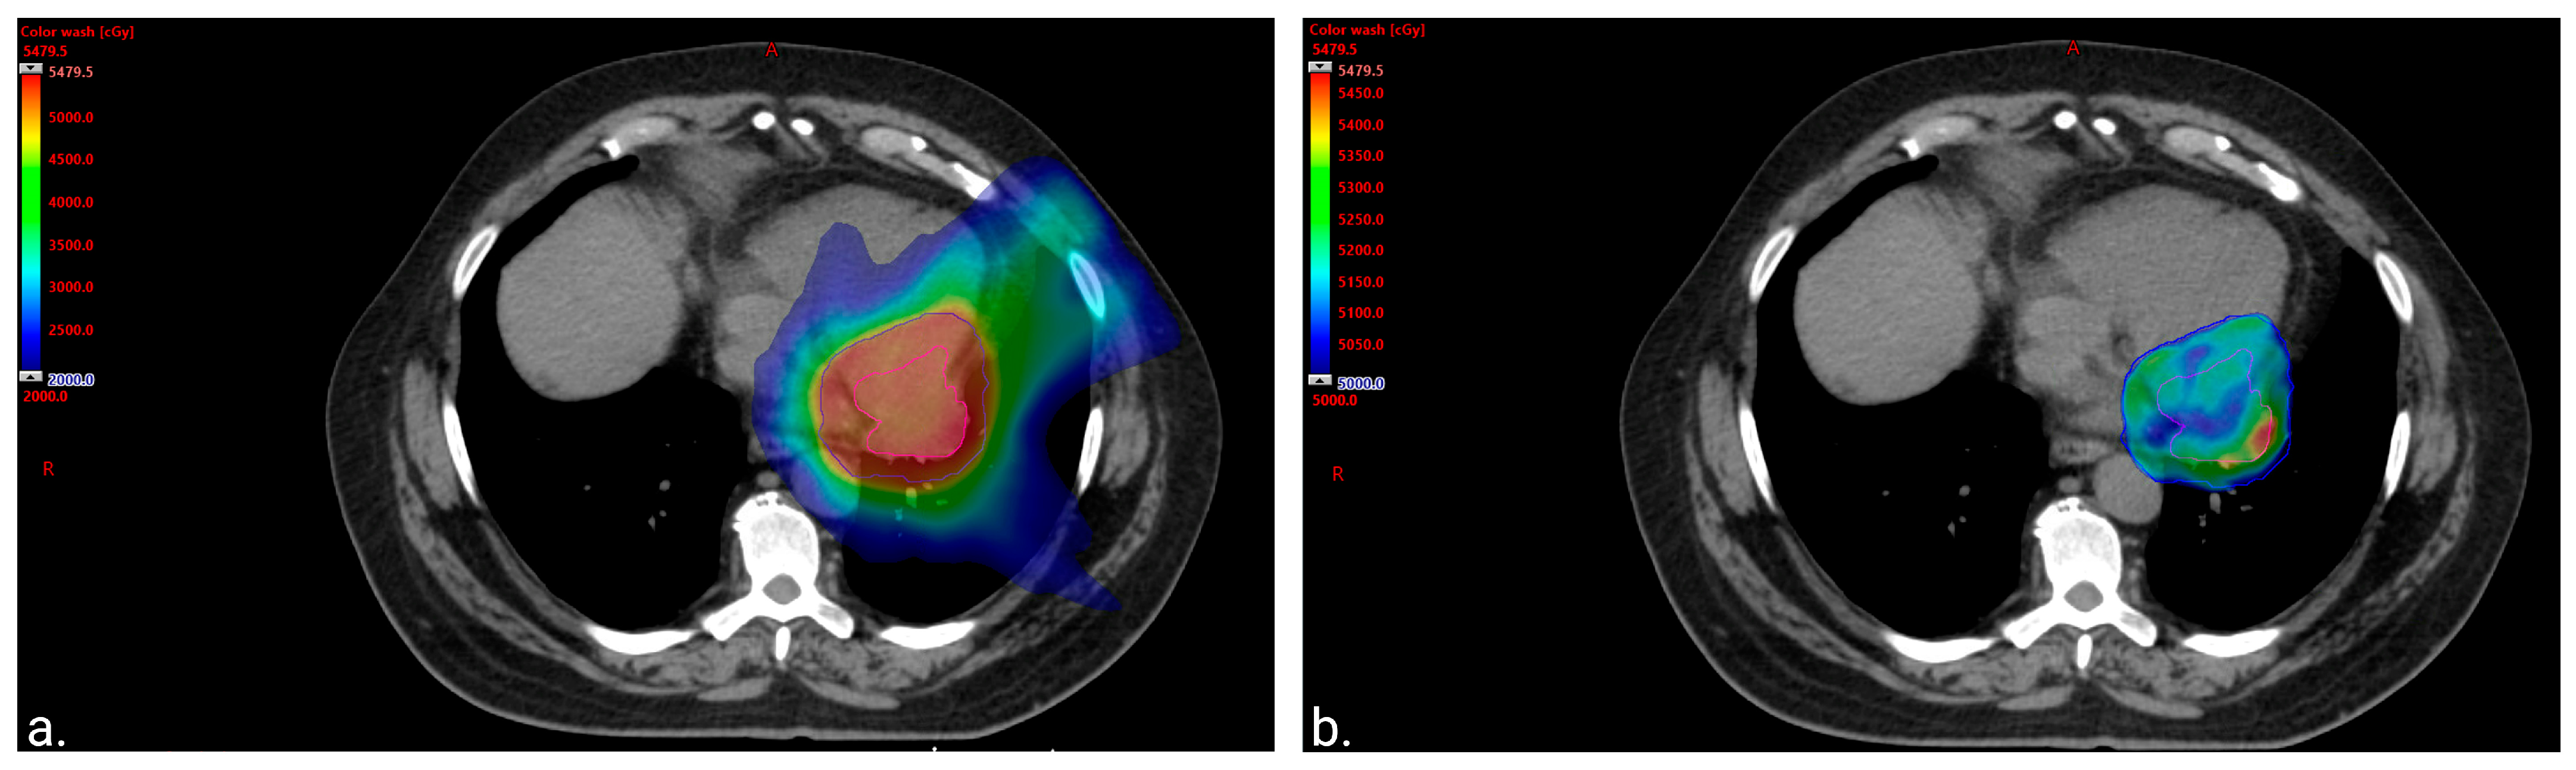

Metastatic MLPS was confirmed following a video-assisted thoracoscopic surgery (VATS). At the VATS procedure, it was noted that the tumor was not attached to the pericardium at the site of biopsy. The treatment plan included neo-adjuvant chemo- and radiotherapy prior to determining the feasibility of surgical resection, as the original tumor extent was not felt to be amenable to local excision. The patient received four cycles of doxorubicin (30 mg/m2) and ifosfamide (3750 mg/m2) on days 1 and 2 (every 21–28 days) with mesna (750 mg/m2) and growth factor support. This resulted in a modest (~20%) decrease in maximal tumor dimension. He subsequently received 50 Gray (Gy) in 25 fractions, using an intensity-modulated radiotherapy (IMRT) technique, sparing the heart and lungs of high doses (Figure 2). This was delivered with two concomitant cycles of radiosensitizing chemotherapy with mitomycin (6 mg/m2) and cisplatin (45 mg/m2) on day 1 (every 28 days), leading to a decrease in tumor size from 5 × 3.7 cm to 4 × 2.5 cm. Doxorubicin was omitted from the radiosensitizing regimen to minimize the expected cardiotoxicity related to chest irradiation, and the patient was closely monitored but did not display any signs of declining cardiac function. In anticipation of surgery, additional chemotherapy with gemcitabine (900 mg/m2) on day 1 and gemcitabine (900 mg/m2) with docetaxel (75 mg/m2) on day 8 (every 21 days) was initiated. Cycle 3 was dose-reduced by 25%, and the patient received steroids for presumed chemotherapy-induced pneumonitis. Following cycle 3, he developed worsening pulmonary toxicity with a differential diagnosis, including infection and worsening inflammation; thus, chemotherapy was discontinued.

Figure 2.

Color wash images to visually represent the distribution of the radiation. (a). Color wash image of 20 gray (Gy) volume displaying sparing of the lung and anterior heart. The volume of the total lung receiving at least 20 Gy (total lung V20Gy) was equal to 10.6% (left lung V20Gy = 23.4% and right lung V20Gy = 0%). The heart mean dose was equal to 20 Gy with only 75 cubic centimeters (cc) of the treatment volume overlapping with the heart and 150 cc of the heart getting ≥30 Gy. (b). Color wash image of 50 Gy volume displaying sparing of the apex of the left ventricle from the prescription dose.